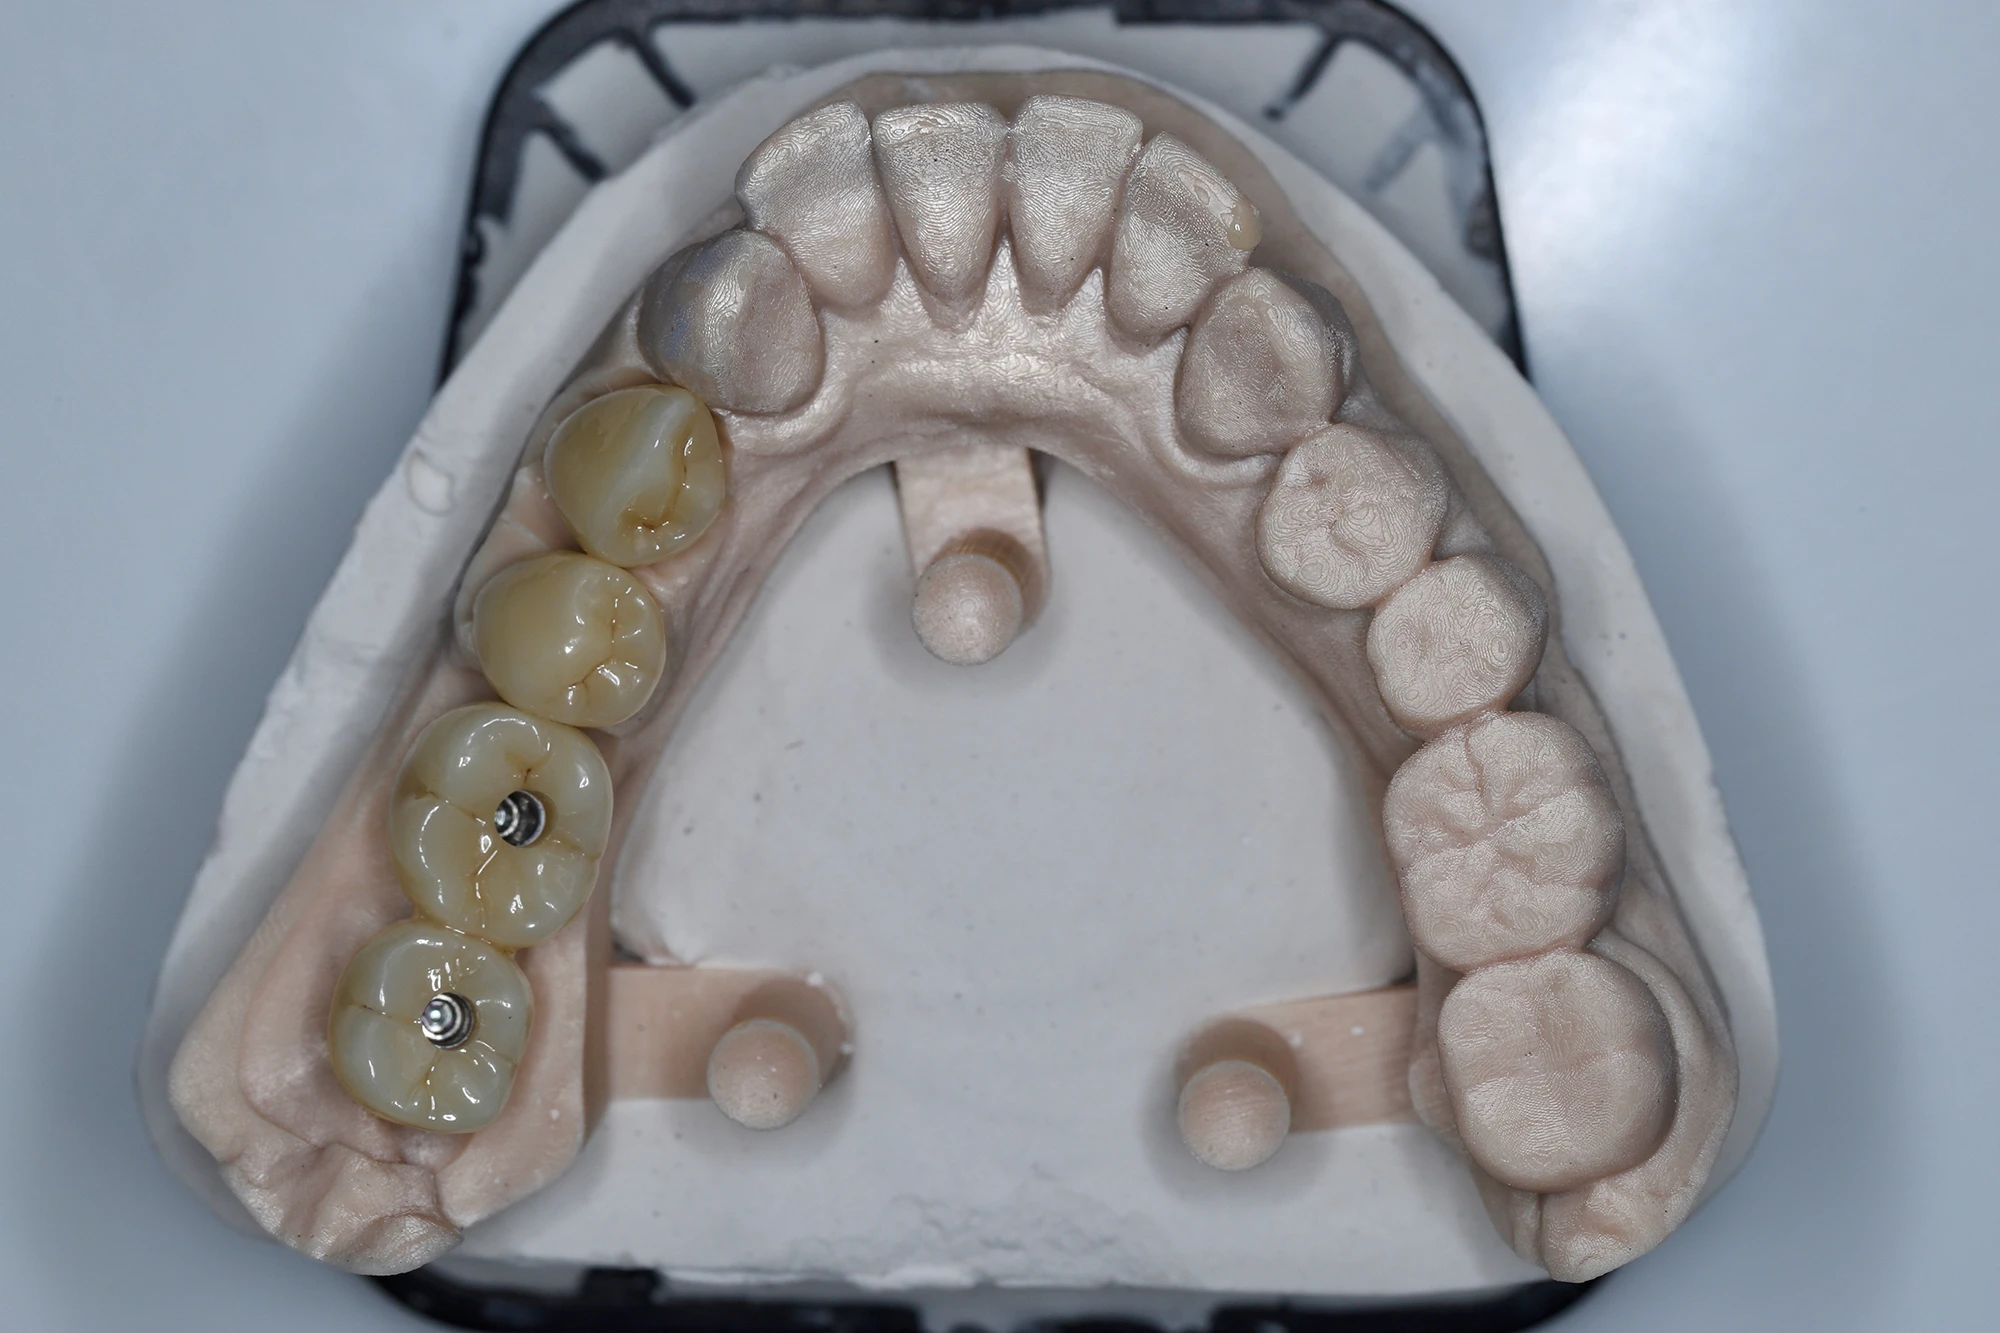

Зубной техник изготовил две циркониевые коронки на имплантатах (36, 37), а также новые полноанатомические циркониевые коронки на 34 и 35 зубы в единой цветовой гамме.

Во время визита пациентки в клинику были проверены посадка ортопедических реставраций, их краевое прилегание, окклюзионные контакты, симметрия и эстетическая составляющая. Пролечен контактный и пришеечный кариес на 33 зубе. Коронки на имплантатах зафиксированы винтовым способом, на своих зубах — на стеклоиономерный цемент.